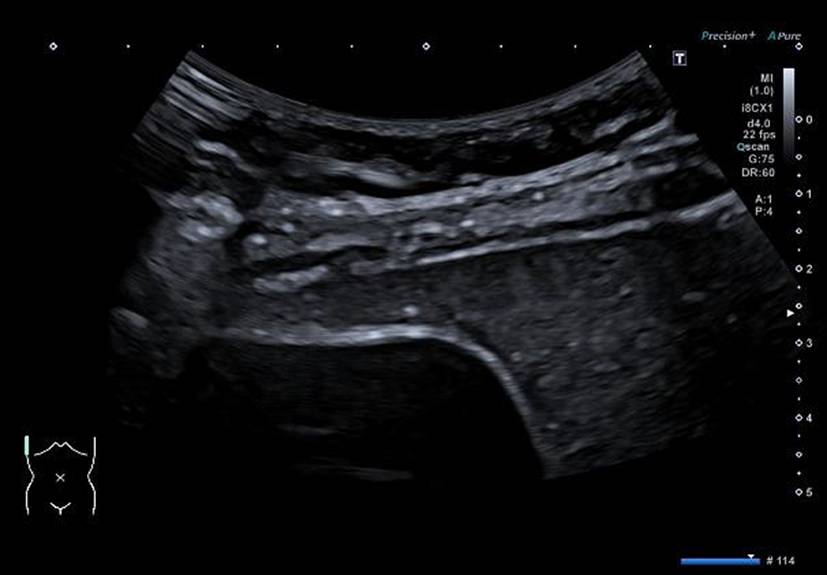

Die alveoläre Echinokokkose (AE) zeigt in der Bildgebung eine breite morphologische Variabilität und kann sowohl zystische als auch solide oder gemischt zystisch-solide Strukturen aufweisen (Abb. 1). Selbst für erfahrene Radiologen ist es oft schwierig, AE-Läsionen von malignen Erkrankungen wie intrahepatischem Cholangiokarzinom oder Lebermetastasen sowie von benignen Veränderungen wie Hämangiomen oder zystischer Echinokokkose zu unterscheiden. Zur Klassifizierung von AE-Läsionen wurden für Ultraschall, CT und MRT verschiedene deskriptive Systeme entwickelt [1315]. Diese haben aktuell vor allem in der Forschung eine Bedeutung. Im Ultraschall erscheint eine AE häufig als avaskulärer, gemischt echogener Tumor mit pseudozystischen oder verkalkten Anteilen, was gelegentlich Hämangiomen oder Metastasen ähneln kann [15]. Ein wichtiger Aspekt in der Bildgebung ist, dass der Nachweis von Verkalkungen nicht als Zeichen einer inaktiven Erkrankung gewertet werden darf [16].

Abb. 1

Verschiedene Präsentationen der alveolären Echinokokkose im Ultraschall. a AE, metastasenähnlich, b AE, hämangiomähnlich, c AE, primär zystisch, d AE, primär solide